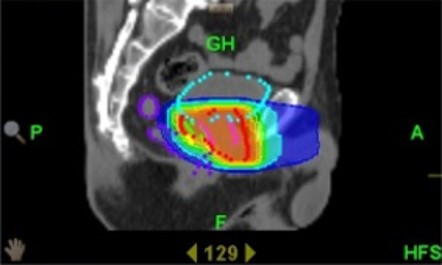

■放射線治療(外照射療法): 外部から放射線を照射し、がんを死滅させる治療法です。現在は、高精度放射線治療である強度変調放射線治療(IMRT)が標準的な治療法とされています。IMRTでは正常組織の被曝を最小限にしつつ、がん組織に放射線を集中的に照射することが可能です。